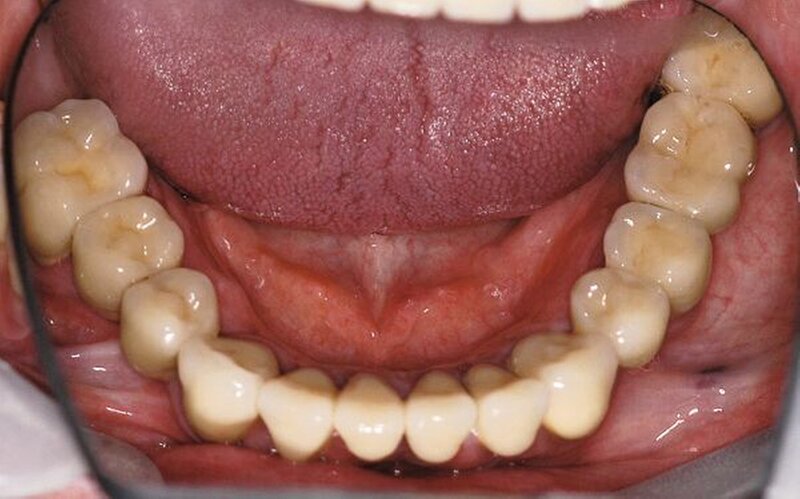

In der darauf folgenden Sitzung wurden alle Kronen und Brücken sowie die teleskopgetragene, partielle obere Prothese für einen Zeitraum von sieben Tagen zum Probetragen mittels eines Zements auf Zinkoxid-Eugenol-Basis eingegliedert. Dem Patienten sollte durch das Probetragen der Restaurationen beziehungsweise des angefertigten Zahnersatzes die Möglichkeit gegeben werden, sowohl die Funktion beim Essen und Sprechen als auch die Ästhetik im sozialen Umfeld zu testen. Ein erneutes Entnehmen der Restaurationen wäre – für den Fall notwendiger Korrekturen – somit ohne Weiteres möglich gewesen. Da der Patient sowohl die Funktion als auch die Ästhetik betreffend keine Änderungswünsche vorbrachte und auch keine neuerlichen Beschwerden aufgetreten waren, konnten die Restaurationen nach besagtem Tragezeitraum von sieben Tagen entnommen, gesäubert und mittels eines Glasionomerzements definitiv befestigt werden. Im Anschluss wurden erneut Situationsabformungen der Kiefer genommen und der Patient erhielt nach erneutem Checkbiss-Registrat, eine okklusal adjustierte Stabilisierungsschiene im Unterkiefer. Diese dient der Therapie der beschriebenen Bruxismusproblematik und gewährleistet einen langfristen Erfolg der eingegliederten prothetischen Restaurationen (Abbildungen 13a, 13b, 13c, 14, 15a, 15b, 15c).

Abschließend kann somit festgehalten werden, dass durch die gewählte Restaurationsform sowie durch die Art der technischen Umsetzung ein funktionell und ästhetisch sehr gutes Ergebnis erreicht werden konnte. Die Prognose des angefertigten Zahnersatzes ist bei entsprechender Compliance des Patienten sowie aufgrund der guten werkstofftechnischen Eigenschaften über einen Zeitraum von vielen Jahren als sehr gut einzustufen (Abbildungen 16a, 16b, 16c, 16d, 16e ).